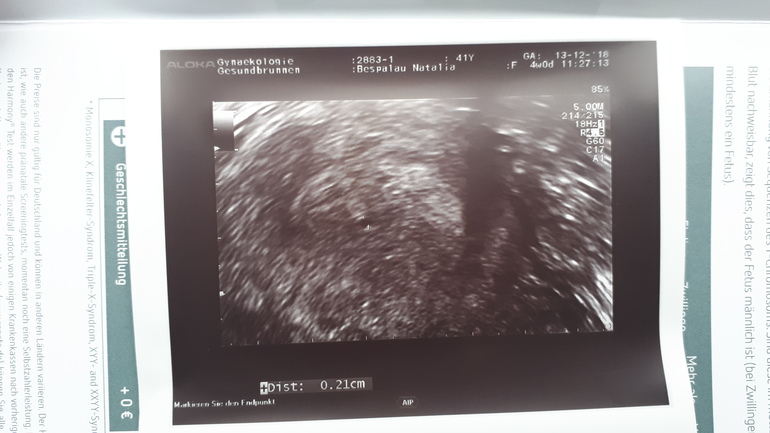

Девочки, серьезный для нас вопрос! После 5и месяцев самостоятельной ЕБ врач направляет нас на ЭКО. Все анализы сдавали, все в полном порядке у обоих, но нам 41 и 44г. Никакой альтернативы ЭКО нам не предлагают. Три месяца пили витамины Д и фолиевую, утер...